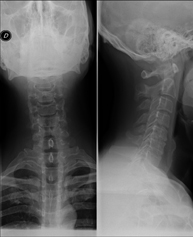

- RX Columna cervical

Tècnica que usa els raigs X a través de la qual s'obtenen imatges de la columna cervical per al seu estudi. Indicacions: traumatisme, contractura cervical, dolor articular. - RX Ossos propis nasals

Tècnica que usa els raigs X a través de la qual s'obtenen imatges de la columna cervical per al seu estudi. Indicacions: traumatisme, dolor cervical. - RX Columna dorsal